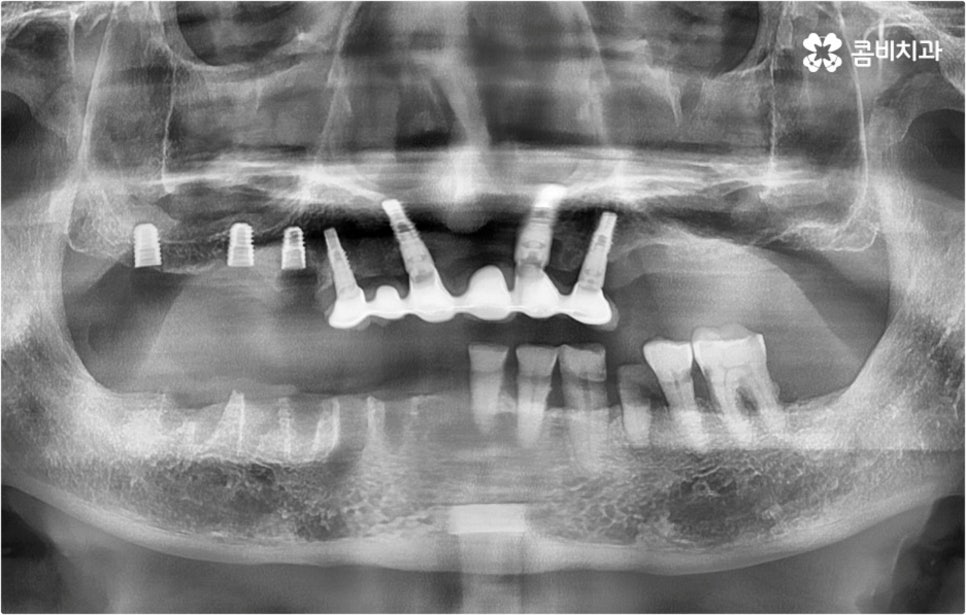

이때 환자분들의 상황에 따라서 임플란트 시술이 어려운 분들도 있을 수 있고 시술 전에 다른 치료를 선행해야 하는 분들도 있을 수 있기 때문에 먼저 꼼꼼하게 검진을 받아보실 필요가 있습니다. 특히 대다수의 치아를 잃어버리고 전악임플란트 를 진행하시는 분들의 경우 원인에 따라서 대처 방법이 다를 수 있는데요.

예를 들어 사고를 통해 한꺼번에 여러 개의 치아가 부러지거나 빠진 경우 연령 또는 전신 질환 여부 등을 살펴보고 치조골 상태가 양호하다면 보다 빠르고 간편한 당일 식립 방식을 이용해 볼 수 있어요. 그러나 하나 둘씩 치아가 빠질 때 마다 제때 치료를 해 주지 않아 치료 시기를 놓치고 결과적으로 무치악 상태에 이른지 오래 된 경우 또는 틀니를 오래 착용하여 잇몸뼈가 이미 많이 내려앉은 경우라면 바탕이 되는 잇몸뼈를 보충해 준 후 식립을 진행하는 방식을 이용해야 할 거예요.

아무 것도 없는 상태에서 제대로 저작 기능을 발휘할 수 있도록 다시 구강 내부를 재현하는 전악임플란트 는 굉장히 고난도에 속하는 치료이기 때문에 충분한 임상 경험을 가지고 있는 숙련된 의료진과 함께 하실 필요가 있어요. 전악임플란트 방식이 빠진 영구치 자리마다 다 임플란트를 식립하는 것이 아니라, 상하악 각각에 8~12개 정도로 필요한 최소한의 인공 치근을 심고 그 사이 사이는 브릿지 방식으로 보철물을 연결하는 것이기 때문에 저작력을 골고루 분담하여 안정적인 지속성을 높일 수 있도록 환자 개개인의 상태에 맞게 인공 치근의 위치, 각도, 간격, 심는 깊이 등을 세밀하게 설정하여 교합을 제대로 맞출 수 있는 시술자의 뛰어난 기술력과 풍부한 노하우가 요구되는 거예요.